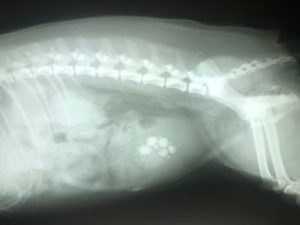

If this happens, your vet is likely to test the urine with a dipstick looking for cells and crystals under the microscope. With smaller dogs, a vet may be able to feel larger stones in the bladder. Some stones may show up with standard X-rays, others with ultrasound.